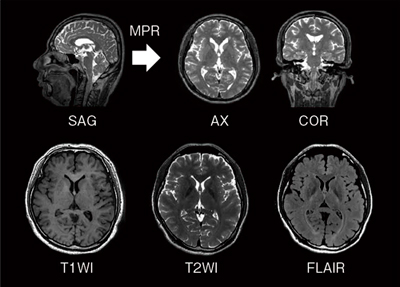

高精細volume imaging 撮像機能“isoFSE”

“isoFSE”は,アイソボクセルの高速3D撮像機能です。FSEの反転パルスのフリップアングルを可変として,マルチエコーの信号強度変化から生じる影響を抑制し,高精細な3D撮像を可能とします。この可変パターンを最適化することで,T1強調画像,T2強調画像,FLAIR画像の高いコントラストを実現しました。

撮像した高空間分解能のボリュームデータから,MPR処理で任意断面の画像再構成も可能です(図4)。

図4 Volume imaging 撮像機能“isoFSE”